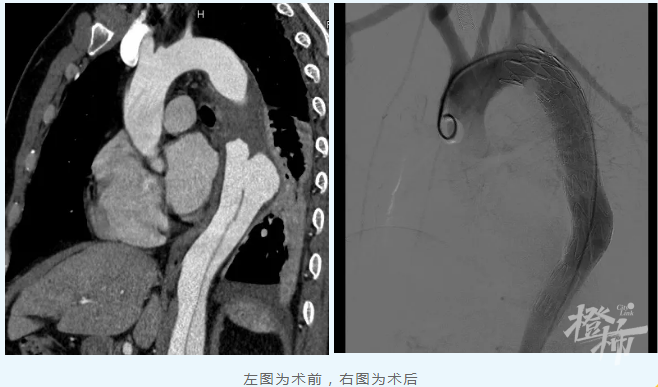

浙江省立同德医院血管外科医护团队第一时间为其进行了充分的病情评估和细致的沟通,并立即收治入院密切监护治疗。经过一段时间积极监护治疗、充分评估和完善相关准备后,血管外科严金副主任医师团队DSA(血管造影术)下在周先生主动脉腔内精准置入覆膜支架隔绝修复夹层破口。术后第一天,周先生就能正常下床活动,第四天康复出院。